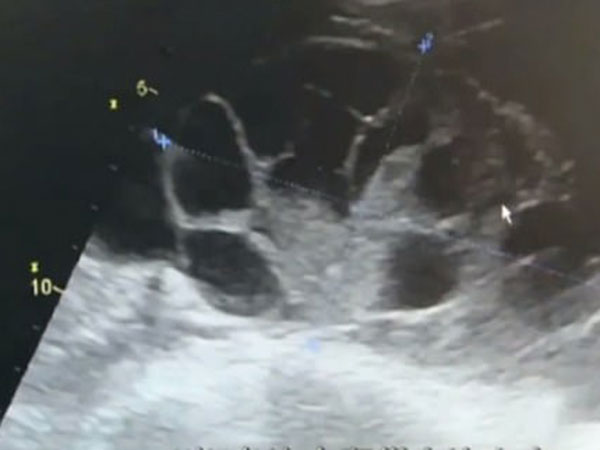

അണ്ഡോല്പാദനത്തിനായി ഓവറികള് കൂടുതല് ഉത്തേജിപ്പിച്ചതു കൊണ്ടുള്ള ഒവേറിയന് ഹൈപ്പെര് സ്റ്റിമുലേഷന് സിന്ഡ്രോം ആണ് ഈ യുവതിയ്ക്കു വന്നത്. ഇത്തരം അവസ്ഥയെക്കുറിച്ചോ ഇതുണ്ടാക്കുന്ന ആരോഗ്യപ്രശ്നങ്ങളെക്കുറിച്ചോ ഈ പെണ്കുട്ടിയ്ക്കു വിവരിമില്ലായിരുന്നു.

ഈ കുത്തിവയ്പുകളെ തുടര്ന്ന ഈ പെണ്കുട്ടിയുടെ ശരീരത്തില് 7 ലിറ്ററോളം വെളളം കെട്ടിക്കിടന്നിരുന്നു മാത്രമല്ല, ഓവറികള് 7 മാസം ഗര്ഭമുള്ള സ്ത്രീകളുടേതിനു സമാനമായിരുന്നു.